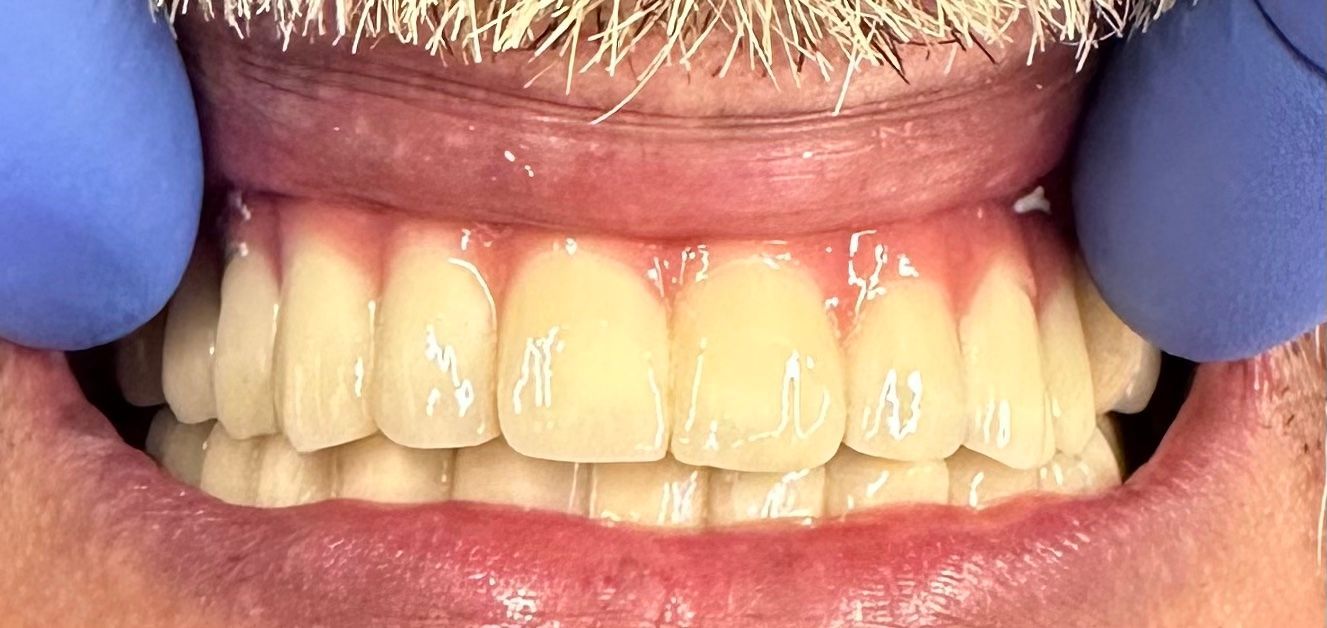

UN'EMERGENZA DENTALE / FOTO 2

ButtonLo scopo principale del trattamento è quello di ricostruire i monconi per poter realizzare immediatamente un ponte fisso, poiché la paziente non accetta una protesi mobile.